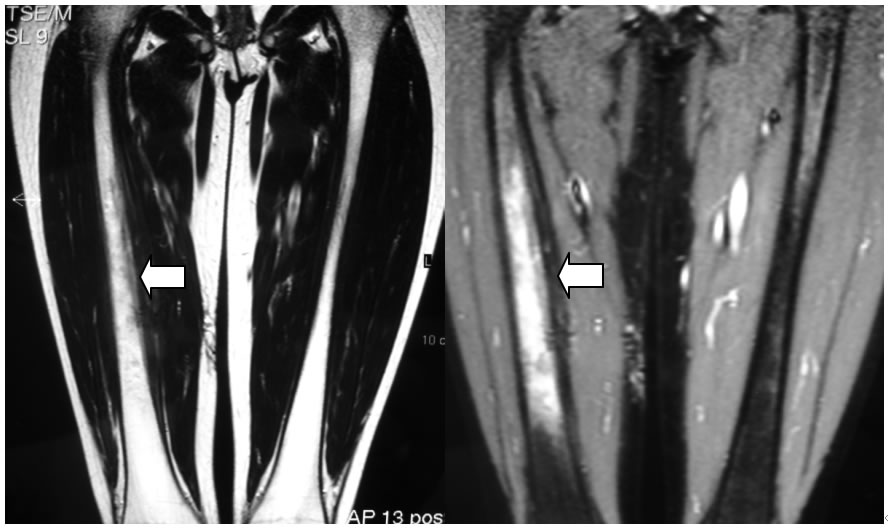

Visto il recidivare della sintomatologia a due anni dall'esordio, in una lesione monofocale, preoccupati comunque di poter perdere una diagnosi di tumore �prendiamo tempo� con l'esecuzione di una RMN (figura 3a, figura 3b), che nuovamente esclude una malignit�, con un quadro nel suo complesso compatibile con diagnosi clinica diOsteomielite-Periostite.

Figure 3a,b: RM, piani coronali con mezzo di contrasto (T1) confermano il reperto e mostrano una marcata vascolarizzazione a tale livello.